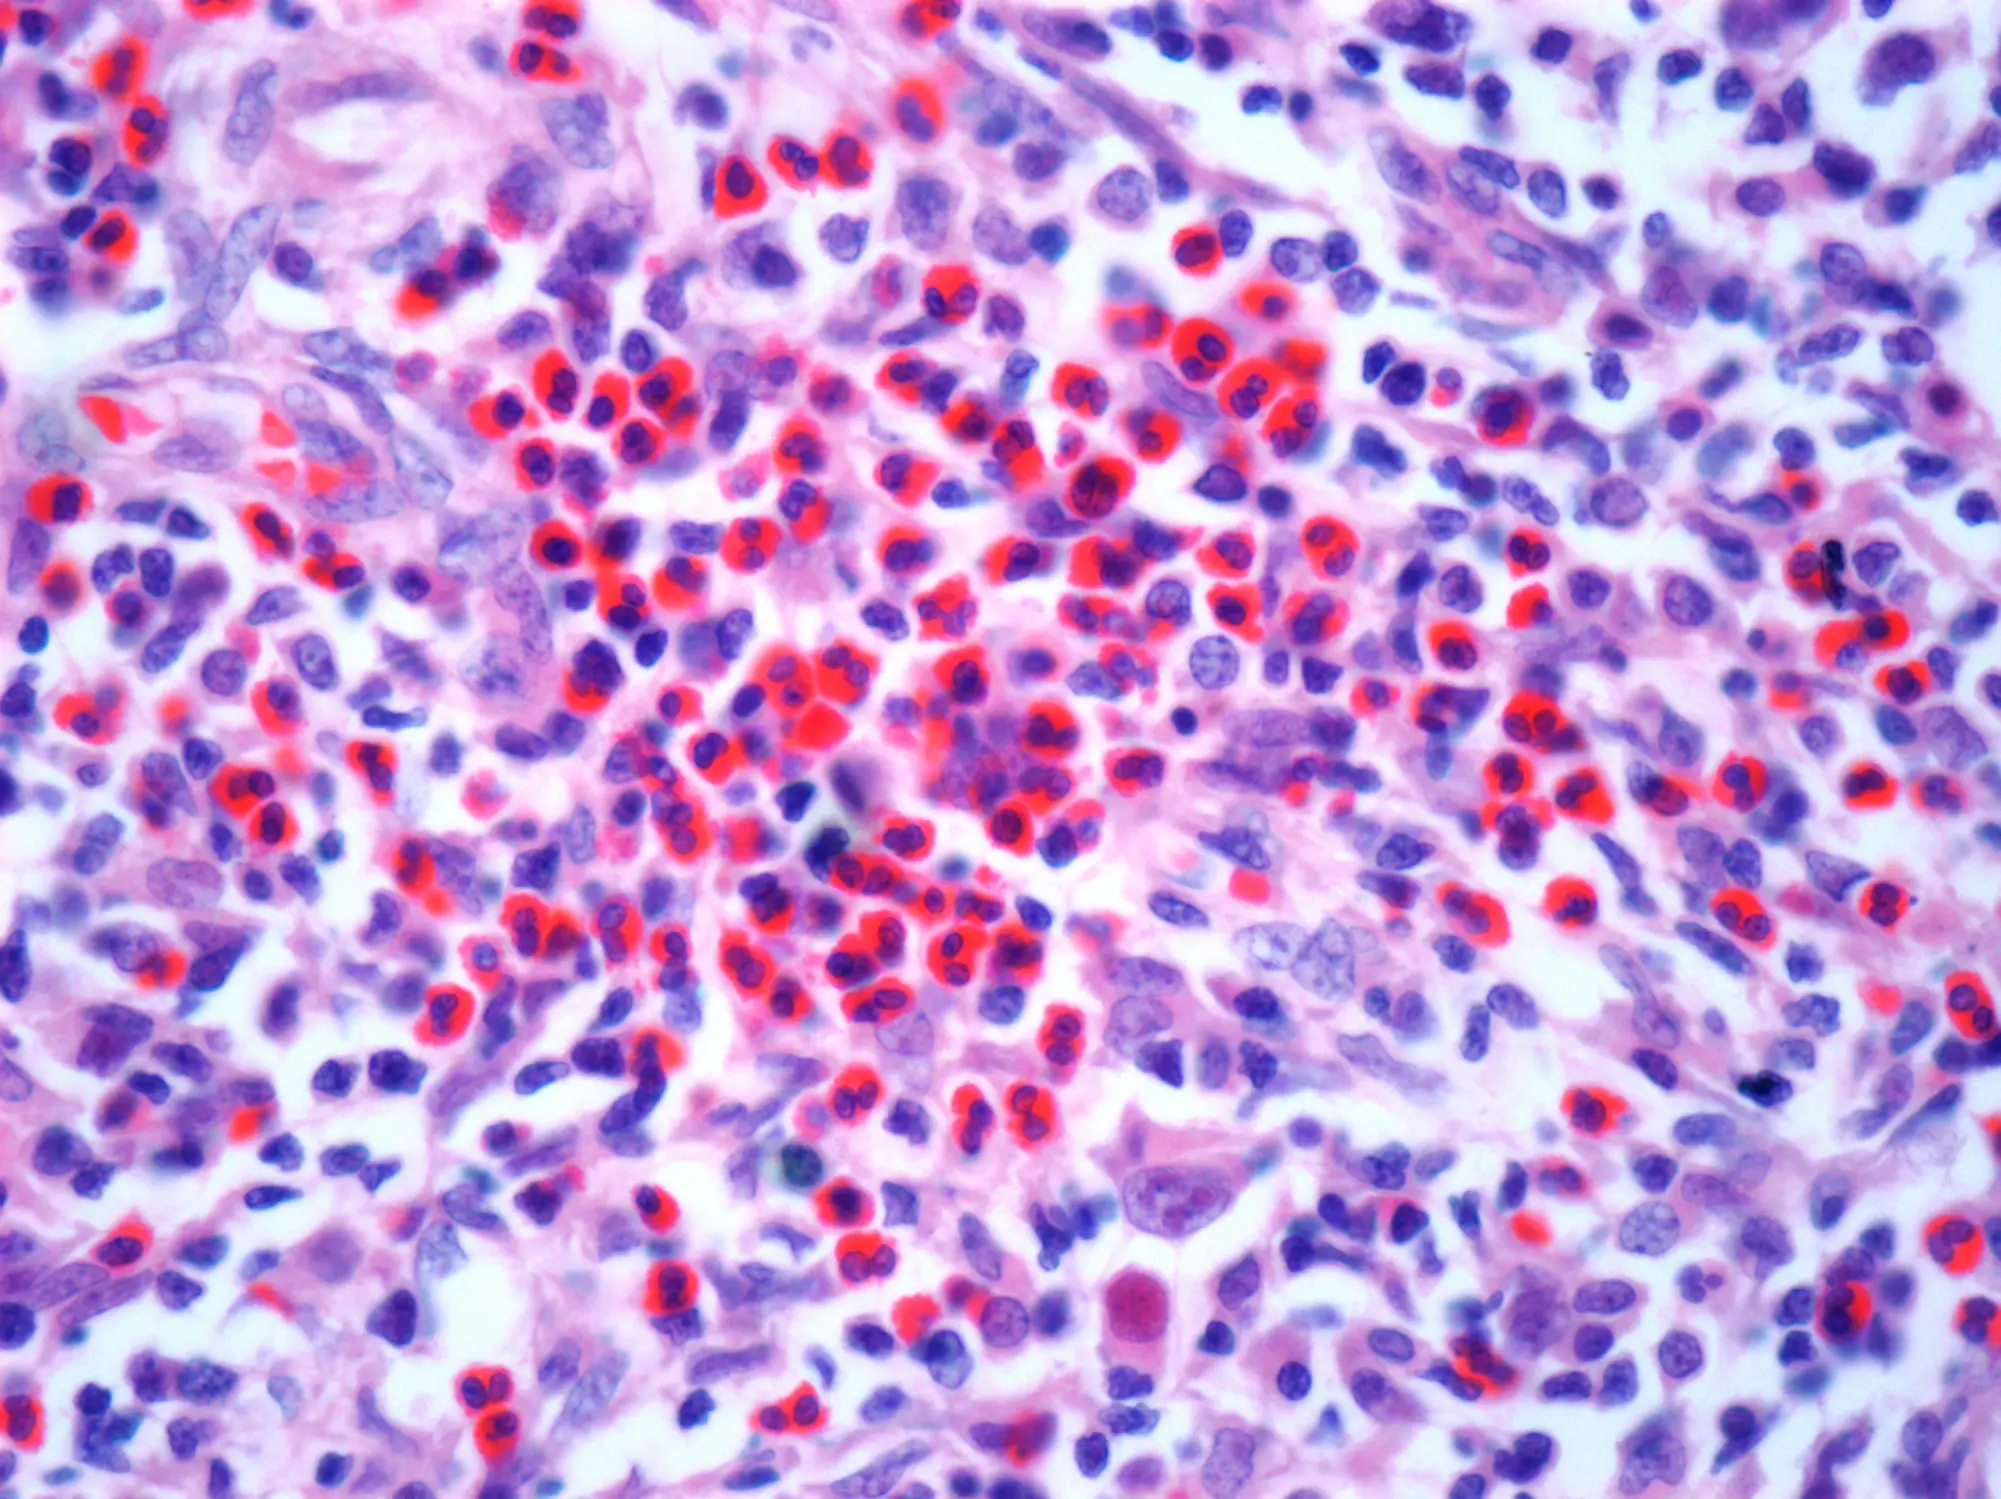

It was during this time that he was diagnosed with Hodgkin lymphoma, a type of cancer that develops in the lymphatic system.

Hodgkin lymphoma mostly affects people between the age of 20 and 40 and those over 75, with slightly more men than women diagnosed with the illness.

It is a relatively aggressive cancer and can quickly spread, but it is also one of the most easily treated.